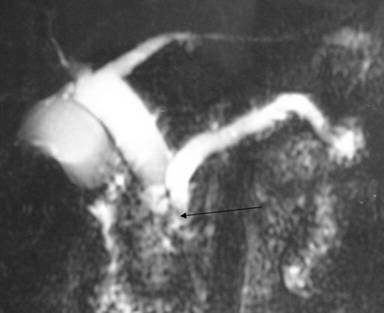

A 35-year-old male suffered from colicky abdominal pain in the right hypochondrium and epigastrium of four months duration, not associated with jaundice or weight loss. On admission, his total bilirubin was 0.7 mg/dL, AST 23 IU/L, ALT 15 IU/L, alkaline phosphatase 104 IU/L, GGT 9 IU/L and amylase 112 IU/L (reference ranges: 0-110 IU/L). A CT scan showed atrophy of the pancreas with a 1 cm dilatation of the pancreatic duct (Figure 3a). A calculus was seen in the pancreatic duct near the ampulla (Figure 3b). Diffuse dilatation of the common hepatic duct and the common bile duct was seen without any calculus, suggestive of a choledochal cyst. MRCP confirmed this finding and also showed significant atrophy of the pancreas; a pancreatic duct 1 cm in diameter (Figure 4) and an isointense filling defect was seen in the pancreatic duct at its distal end near the ampulla. A diagnosis of chronic calcific pancreatitis with type I choledochal cyst was made. He underwent choledochal cyst excision with a cholecystectomy, hepaticojejunostomy (end-to-side) and side-to-side pancreaticojejunostomy. Tissue from the head of the pancreas confirmed the diagnosis of chronic pancreatitis. Surgery and recovery were uneventful. He is asymptomatic after a 4 month follow-up.

Figure 4. MRCP showing a type Ic choledochal cyst with a dilated pancreatic duct and filling defect seen proximal to the ampulla (arrow). |